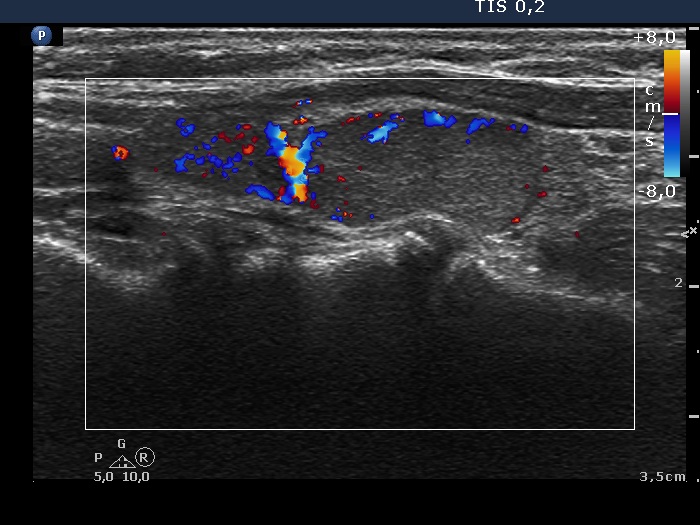

Follow-up examination 3 years later (second row of images):

Ultrasonography: The thyroid was unchanged. The lesions in the dorsal part of the right lobe increased in size and a small hypoechogenic area appeared in the ventral part of the left lobe.

Wash-out thyroglobulin and parathormone levels were determined, the former was 74.4 ng/mL while the latter was above 474 pg/mL.

A repeat blood test was performed. Serum thyroglobulin resulted in 11.9 ng/mL while serum parathormone level did in 180.7 pg/mL. Serum calcium was 2.94 mM/L, serum phosphorus 0.69 mM/L.

Scintigraphy disclosed parathyroid enlargement not only in the right but even in the left side.

Surgery was performed. Histopathology disclosed hyperplasia of all four parathyroids.